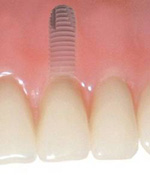

Zubní implantáty jsou umělé zubní kořeny.

Jsou zavedeny do kosti horní nebo dolní čelisti a umožňují náhradu jednoho, několika či všech zubů pomocí korunek, můstků, které jsou na ně připevněny nebo tvoří podporu pro zubní protézy.

Klasickým příkladem a indikací pro použití implantátu je ztráta jednoho zubu (v tomto případě v předním – frontálním úseku) v jinak zdravém, nepoškozeném chrupu.

Při ošetření pomocí jednotlivých implantátů zůstávají sousední zuby neporušené – intaktní. Při klasickém ošetření pomocí můstků musejí být tyto zuby obroušeny!